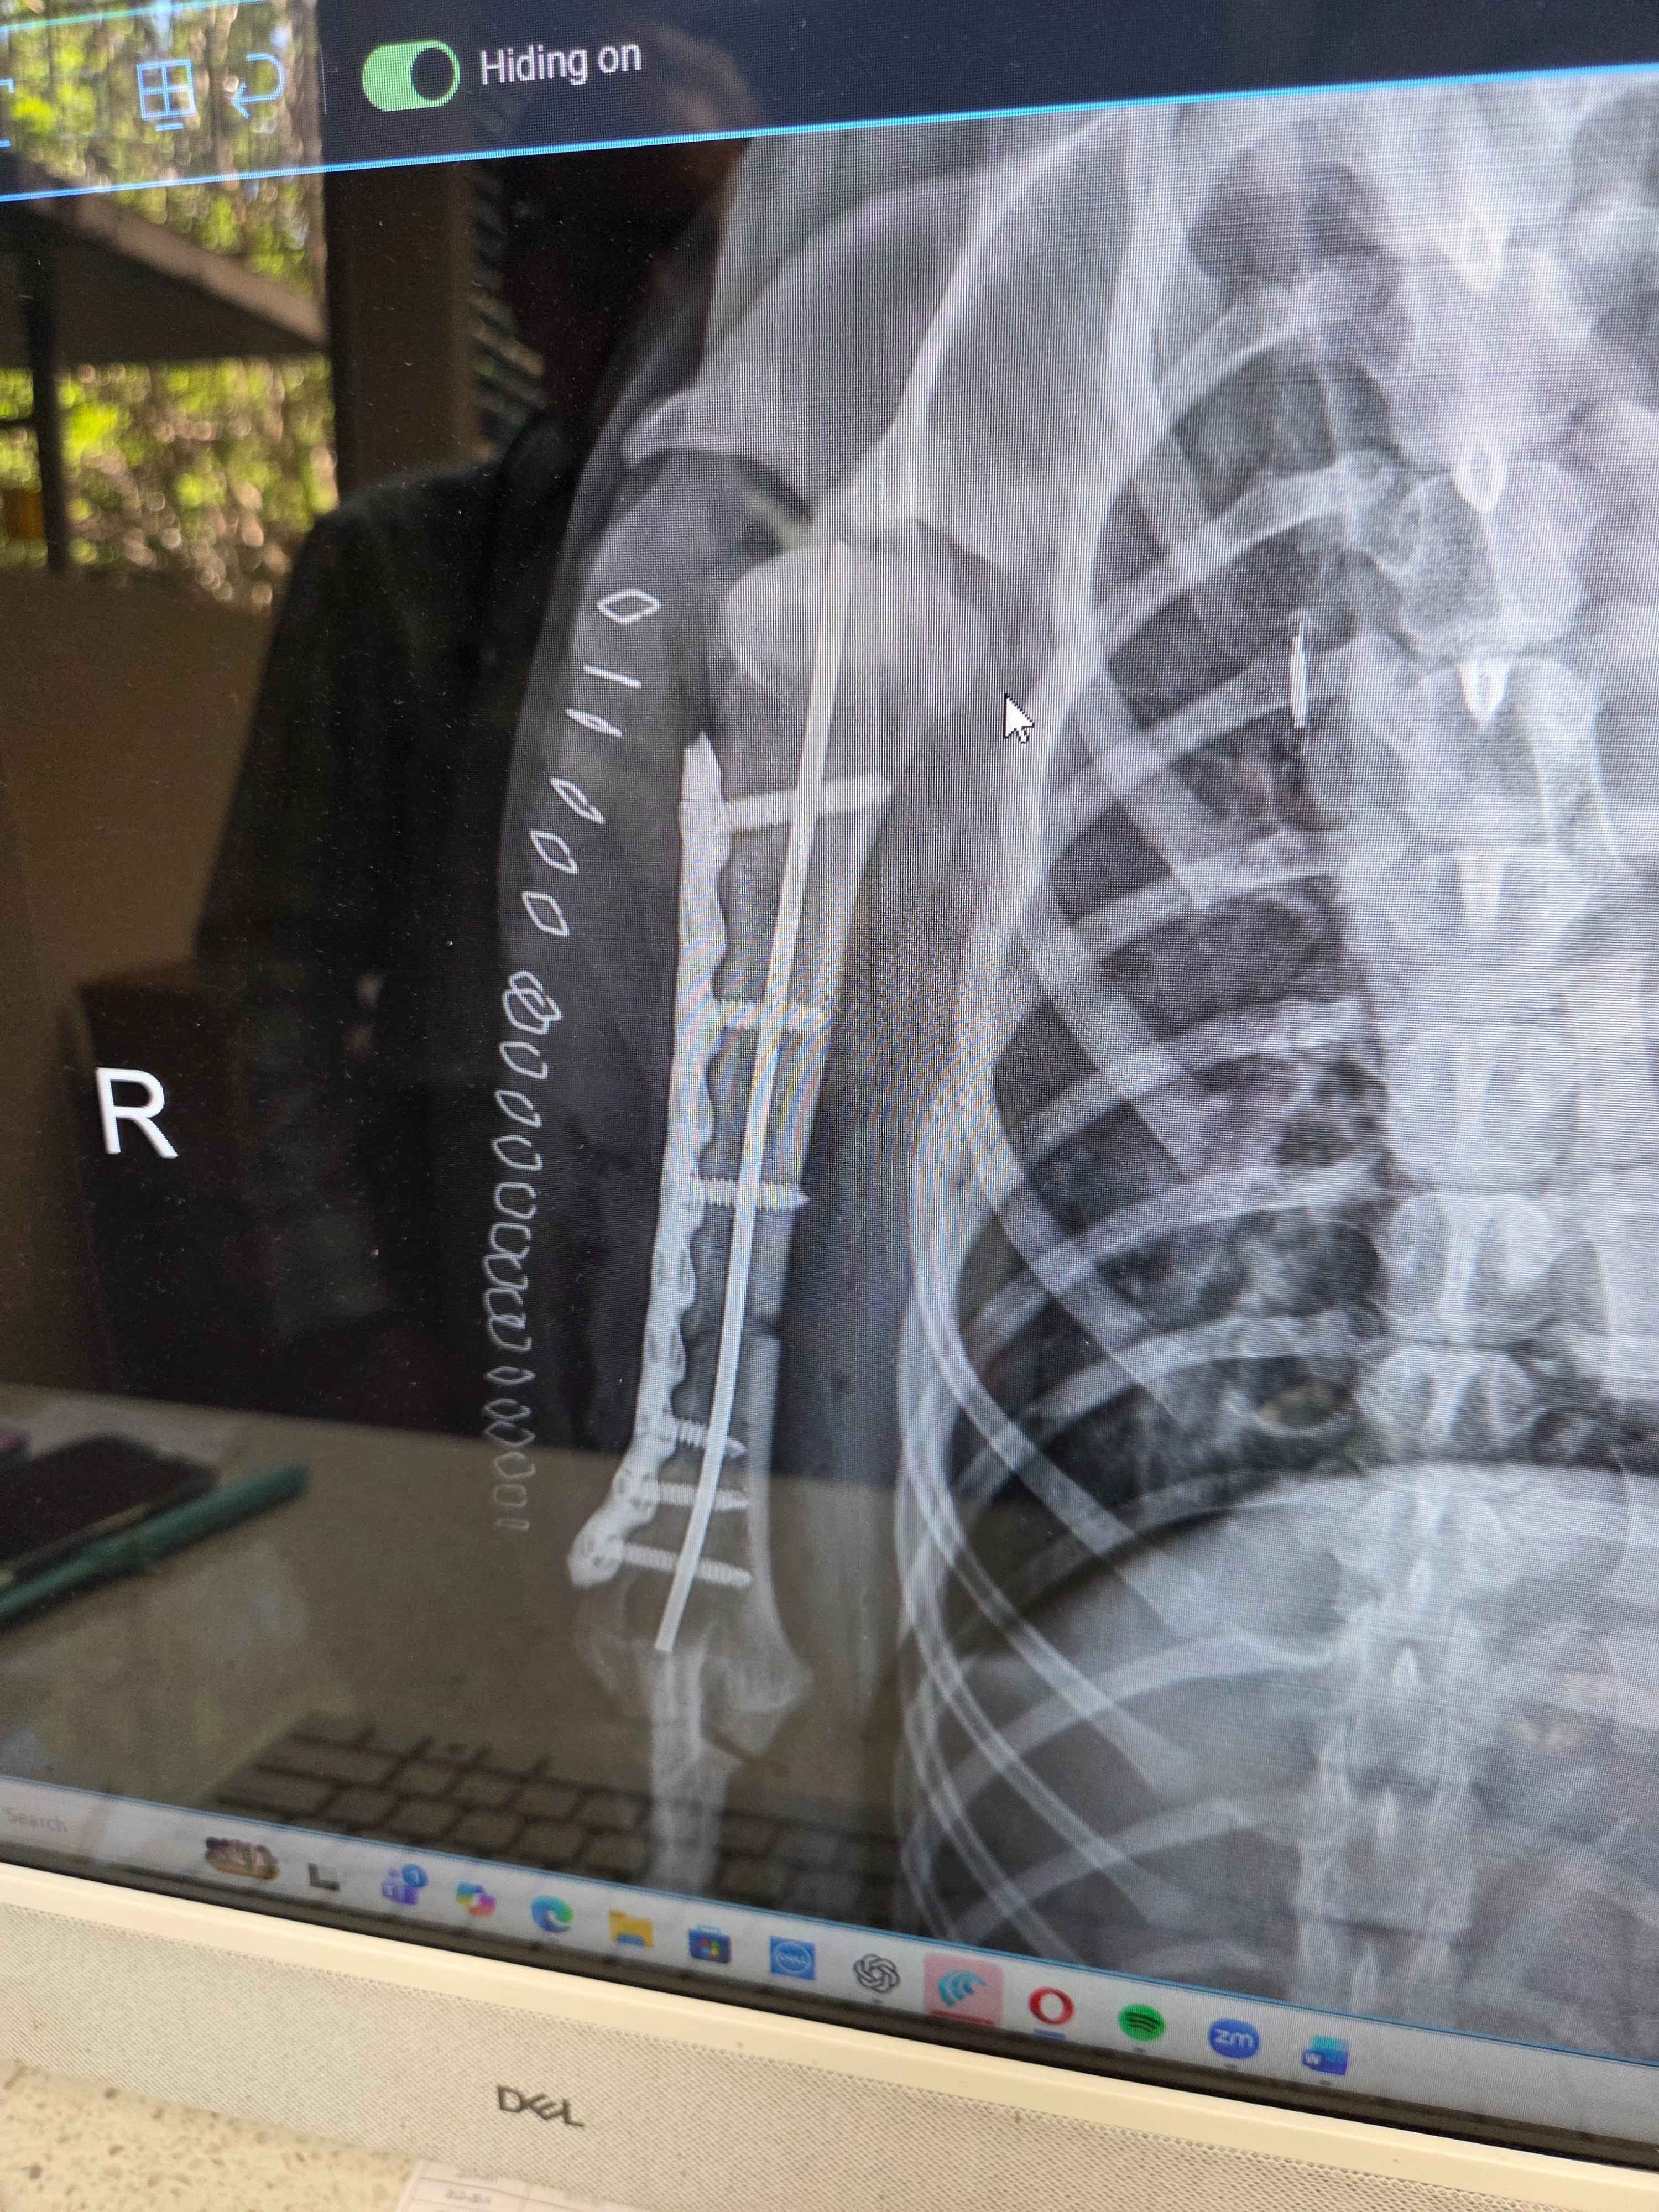

His leg was broken. Not sprained. Broken.

That was the Monday after we got him that we found out. Our little buddy needed a pin and a plate. They said we had about a week to get him in for surgery before amputation could be looked at as a solid possibility. So we vowed that matter what it takes, our sweet Marlow is not losing that leg.

His first surgery was Saturday the 21st with a follow-up surgery on the 24th to adjust the pin in his arm. Both went insanely well and he has nothing but an amazing outlook and life ahead of him!